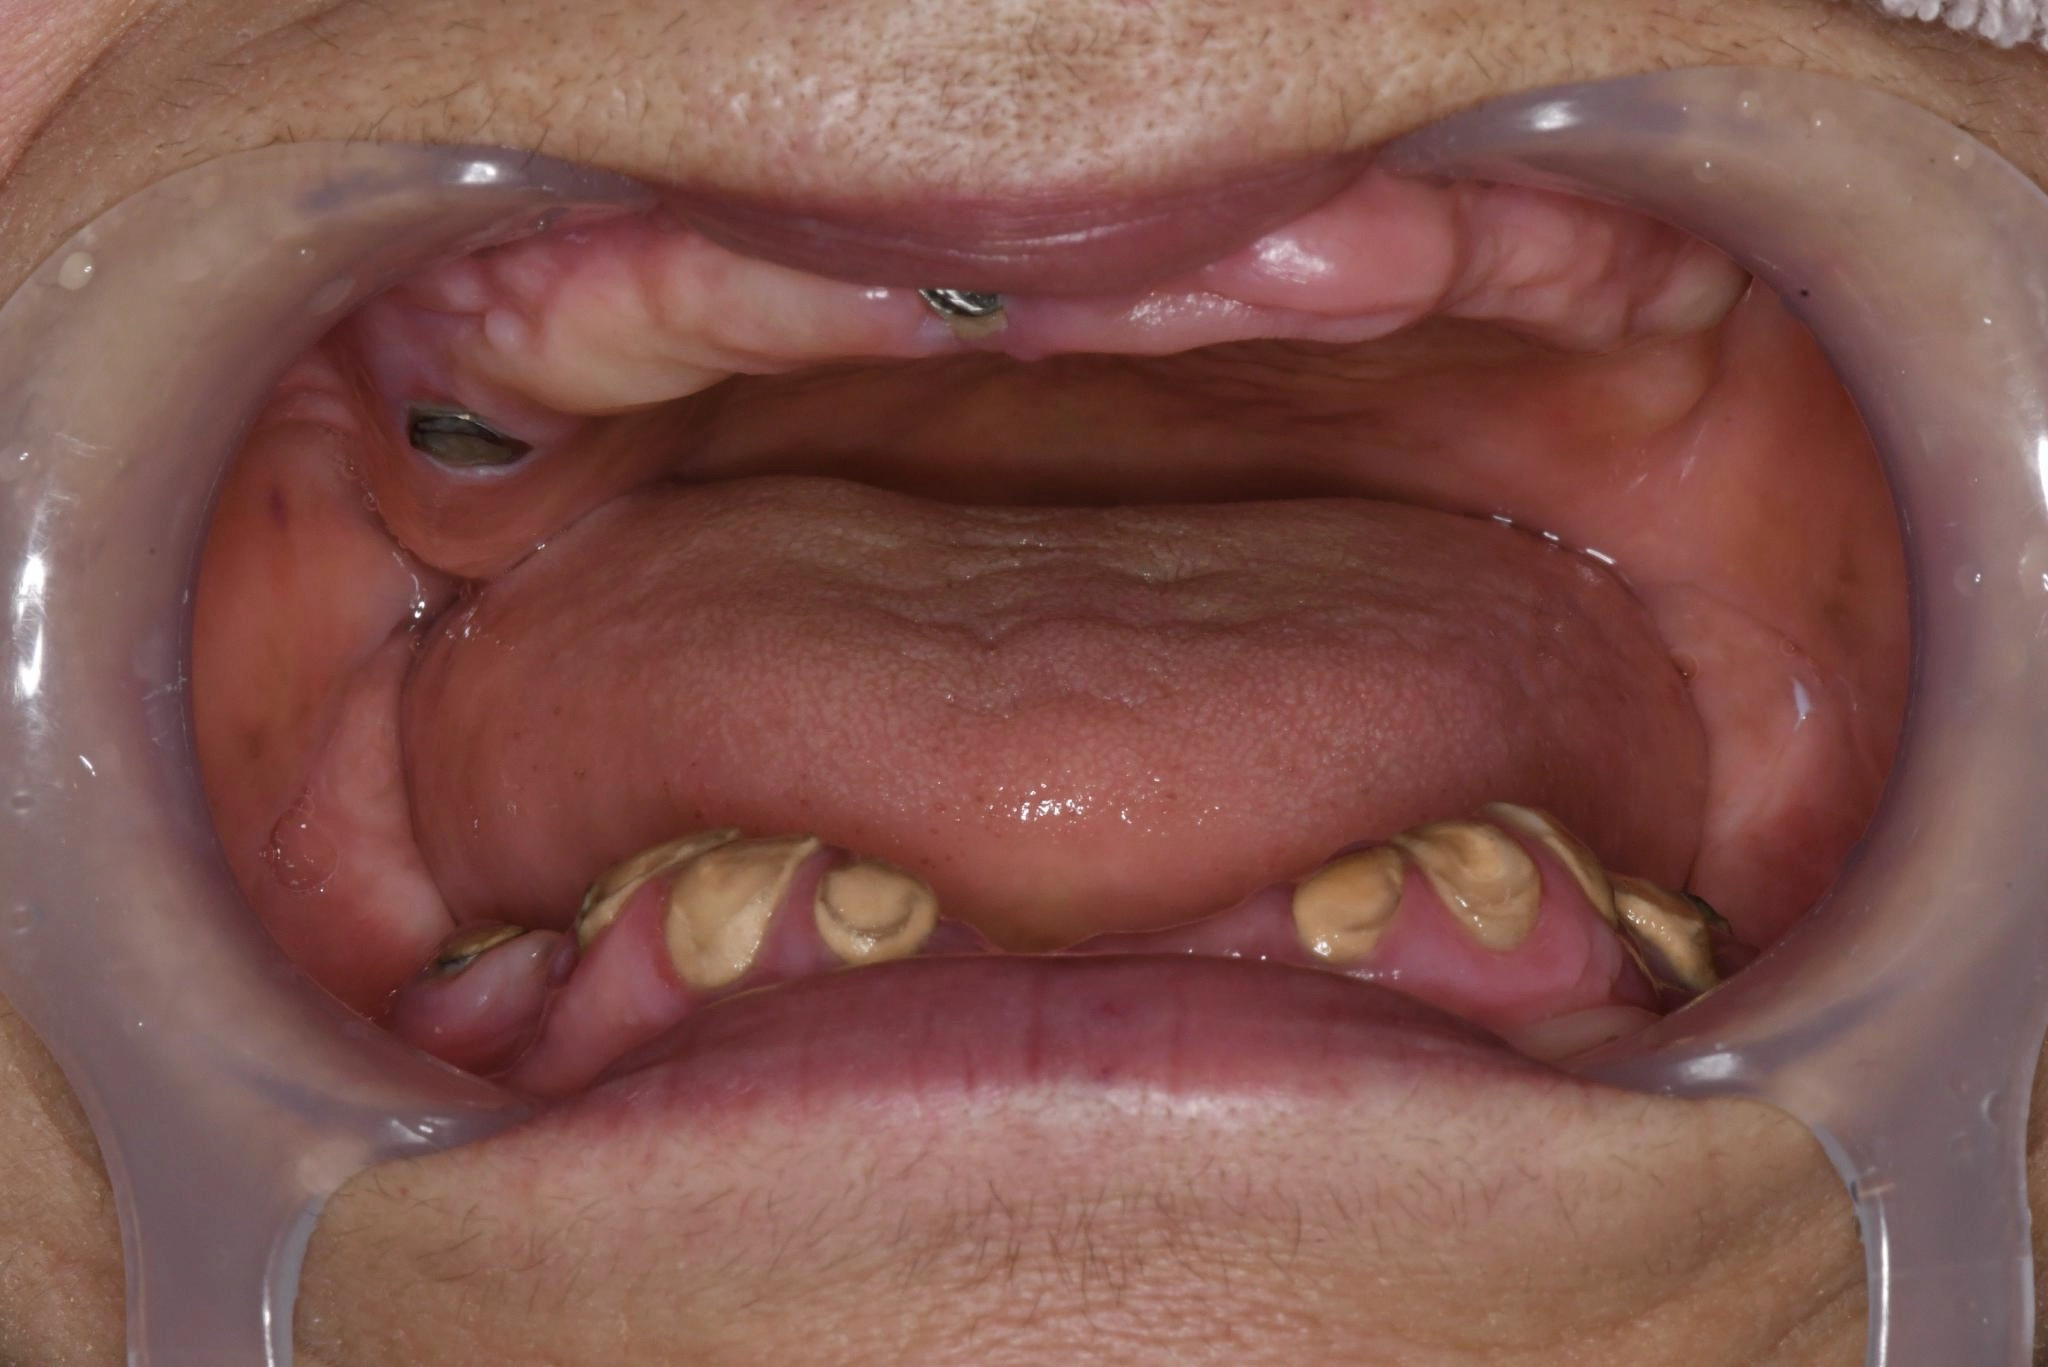

術前

上下総義歯を使用していましたが、食事や会話の度に歯茎に痛みが生じ、日常生活において多大なストレスを抱えていました。情報誌「グランザ」でこちらのクリニックを知り、義歯の悩みから解放されたいという切実な思いから相談に行くことに決めました。

過去に麻酔による全身痙攣の経験があることや骨粗鬆症の治療薬を服用中であることなど外科的処置に対するリスク要因を持ち合わせていました。ですが、丁寧なカウンセリングと説明を受け、取り外し不要な「固定式の歯」を得られることへの魅力が不安を上回り、手術をうけることにしました。